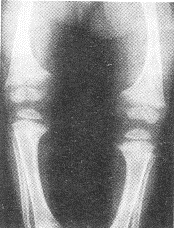

患兒女性,2歲,睡眠差、哭鬧、易出汗;雙腿呈"O"形。X線平片如圖所示。

1.根據(jù)以上臨床資料及影像學(xué)檢查,初步診斷為何病

正確答案:1.D;2.ABDEF;3.ABCDEF 解題思路:長骨的骨干可因骨膜下骨樣組織形成而變粗,且邊緣模糊。